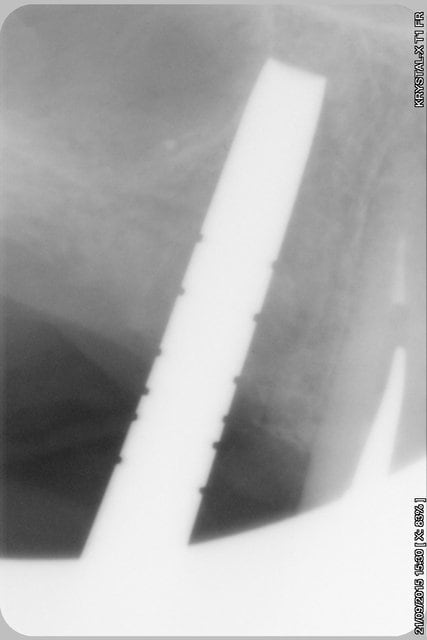

La rx avec bistouri en place sert à vérifier quoi?

la radio sert à vérifier la position de la lame 15, par rapport à la racine et au sinus, mais je ne suis pas sur que tu comprennes, que le bistouri est dans l'os, c'est l'instrument le plus fin et le moins traumatisant pour fendre l'os (je le préfère au piezzo et même au disque diamanté).